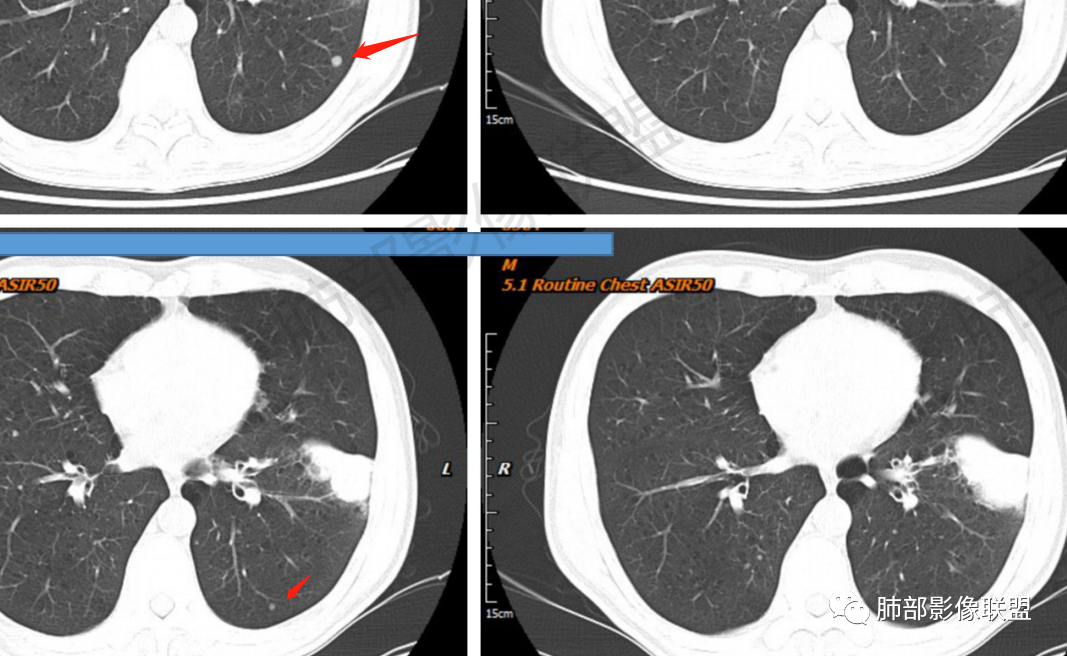

一切∮随缘:左肺下叶不规则肿块,边缘光滑,平直,局部彭隆,分叶,近端支气管堵塞,远端与胸膜相贴,平扫密度尚均匀,增强后不均匀强化,内部可见低密度坏死,胸膜下多发肺气肿,伴双肺散在光滑小结节,实验室肿瘤标志物高,考虑恶性:神经内分泌癌(大细胞),腺癌,鳞癌。

琦遇:恶性没有问题,肺气肿底子、病灶分叶、少许毛刺、叶间胸膜凹陷、部分边缘可见清晰的GGO、胸膜牵拉凹陷、局部胸水、近端支气管截断、部分支气管被推移、占位效应明显、强化特点为不均匀强化、内部有少许沼泽样低强化区,强化部分轻中强化为主、余肺可见转移性结节、左肺上叶似为囊腔型腺癌一枚,肿瘤标志物提示非小、神经内分泌,综合分析考虑大神泌、腺癌、腺鳞癌、鳞癌  同时左肺上叶囊腔型腺癌  肺转移

飞鹰行动:中年人,男性,胸疼入院,左肺下叶占位,张力较高,边界可见分叶,局部可见明显收缩性改变,增强病灶内部有延迟强化表现,考虑恶性病变,大细胞癌伴肺内转移或者囊腔样腺癌伴转移。

蕊:中老年男性,吸烟史,肺气肿背景,左肺上叶类圆形肿块影,边界清晰,边缘凹凸不平,有分叶,支气管进入阻断,临近胸膜栽赃,整体病灶膨隆,局部周围可以清晰ggo,临近叶间裂内凹,轻度强化,并可见多个低密度区,坏死可能,界线不清;肺内多结节,边缘光滑,考虑恶性伴转移,鳞癌、腺癌

傅昌瑜:中老年男性,肺气肿背景,右胸背疼痛1周。CEA、NSE、CYFRA—211升高。左上肺混合磨玻璃结节,内见较多空泡和扩张支气管。左下肺胸膜下肿块,边缘较光滑,深分叶,似有血管进入,与支气管关系不清,内见不均匀强化,见沼泽地样坏死,有胸膜栽赃。另两肺多发圆形小结节。考虑恶性并肺内转移,多原发可能性大,左上肺腺癌,左下肺病理难以判断,小细胞癌?鳞癌?

小锁:中老年男性,肺气肿背景,右胸背疼痛1周。CEA、NSE、CYFRA—211升高。左上肺混合磨玻璃结节,边界清楚,内见较多空泡。左下肺肿块,边缘清楚,深分叶,有血管和支气管进入,胸膜凹陷。另两肺多发圆形小结节。考虑双发原位癌,左上肺腺癌,左下肺大神泌或腺鳞癌可能,肺内转移。

蓝天白云:中年男性,肺气肿背景,左肺下叶肿块,边缘膨隆,有分叶,内有湖泊样坏死,有轻中度强化,局部胸膜栽赃,收缩力不强,周围见肺气肿征象。左肺上叶混合磨玻璃影,边界清楚,考虑都是恶性,左上肺iac,左下肺腺鳞癌,或大细胞肺癌可能。两肺多发结节,考虑转移

毛勤香:老年男性,肺气肿背景,左肺下叶肿块,分叶,边缘光滑,土豆块样,细支气管闭塞,增强轻度不均匀强化,似有坏死,左肺另见多发结节,淋巴结未见明显肿大,恶性确定,吸烟史,鳞癌破坏力强,侵袭力差,多原发的一般很少多于3个,故排后,首先考虑神经内分泌癌,局部血管穿行,鉴别淋巴瘤

周太狼:中年男性,吸烟、高血压史,肿瘤指标升高,肺气肿背景下,左肺下叶肿块影,分叶、膨隆、未跨叶裂,支气管截断,不均匀强化。另双肺多发结节及磨玻璃影,左肺上叶混合磨玻璃,内可见多发空泡影。整体考虑恶性,肺癌伴肺内转移,左下肺鳞癌?神经内分泌癌?左肺上叶囊腔腺癌?